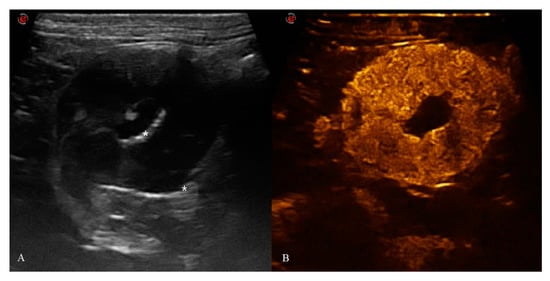

Figure 3. Feline gastric high-grade lymphoma (HGAL): (A) B-mode image of a severe and diffuse hypoechoic wall thickening of 18 mm (between the asterisks) with complete loss of normal wall layers; (B) CEUS examination of the same cat during the peak enhancement of time–intensity curve.

CEUS qualitative assessments were evaluated only for the HGAL since all the cats with a gastric wall thickening ≥6 mm belong to this group. The enhancement patterns of the 10 HGAL on CEUS are reported in Table 4. HGAL showed a variable enhancement degree if compared to the adjacent liver parenchyma (5/10 hyper and 5/10 hypo/iso enhancement). Furthermore, lymphomas of this group were more likely to have a homogeneous enhancement (7/10) and the presence of comb teeth-like vessels (7/10) (Figure 11).